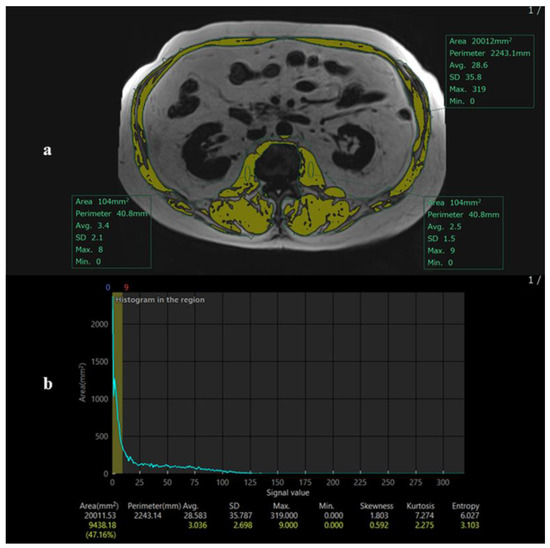

MRI-Based Assessment of Etiology-Specific Sarcopenia Phenotypes in Chronic Liver Disease: A Comparative Study of MASH and Viral Hepatitis

by Mika Yasutomi, Kazuhiro Saito, Yoichi Araki, Katsutoshi Sugimoto, Daisuke Yoshimaru, Shuhei Shibukawa and Masanori Ishida

Diagnostics 2026, 16(2), 306; https://doi.org/10.3390/diagnostics16020306 - 17 Jan 2026

Background: Sarcopenia is a clinically important complication of chronic liver disease (CLD), but its underlying mechanisms may differ according to disease etiology. Quantitative MRI biomarkers, including proton density fat fraction (PDFF) and magnetic resonance elastography (MRE), may help characterize etiology-specific patterns of muscle [...] Read more.

Background: Sarcopenia is a clinically important complication of chronic liver disease (CLD), but its underlying mechanisms may differ according to disease etiology. Quantitative MRI biomarkers, including proton density fat fraction (PDFF) and magnetic resonance elastography (MRE), may help characterize etiology-specific patterns of muscle loss. This study aimed to explore etiology-specific associations between MRI-derived biomarkers and sarcopenia, with a particular focus on metabolic dysfunction-associated steatohepatitis (MASH) and viral hepatitis. Methods: This retrospective single-center study included 131 CLD patients (77 with MASH, 54 with viral hepatitis) who underwent MRI, including PDFF and MRE. Sarcopenia was defined by L2 skeletal muscle index thresholds (<42 cm2/m2 for men, <38 cm2/m2 for women). Muscle identification was performed by automatic threshold-based segmentation by a single observer. Multivariable logistic regression analyses incorporating interaction terms were performed to evaluate whether associations between MRI biomarkers and sarcopenia differed by etiology. Results: Sarcopenia was present in 56% of patients. In the overall cohort, older age (OR = 1.05, p = 0.01), lower PDFF (OR = 0.93, p = 0.03), and lower liver stiffness (OR = 0.51, p = 0.006) were independently associated with sarcopenia. A significant interaction between BMI and disease etiology was observed (p = 0.02). Subgroup analyses suggested that in MASH, sarcopenia was associated with aging, hepatic fat depletion, and lower stiffness. In contrast, in viral hepatitis, it tended to be associated with higher stiffness and lower BMI. Conclusions: MRI-derived hepatic fat and stiffness reflect distinct etiologic patterns of sarcopenia in CLD—metabolically depleted in MASH and fibrosis-related in viral hepatitis. These findings suggest that sarcopenia in MASH and viral hepatitis may reflect different underlying phenotypic patterns, highlighting the importance of considering disease etiology in imaging-based sarcopenia assessment. The results should be interpreted as hypothesis-generating and warrant validation in prospective studies. Full article

(This article belongs to the Section Medical Imaging and Theranostics)

Show Figures

Figure 1